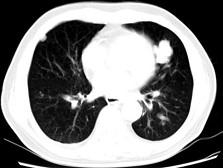

问题 男,64岁,咳嗽半月,咯血一天,不发热,结合影像图像选择最可能的诊断 ( )

选项 A、结节病 B、组织胞浆菌病 C、肺转移性瘤 D、肺结核 E、金葡菌肺炎

答案 C